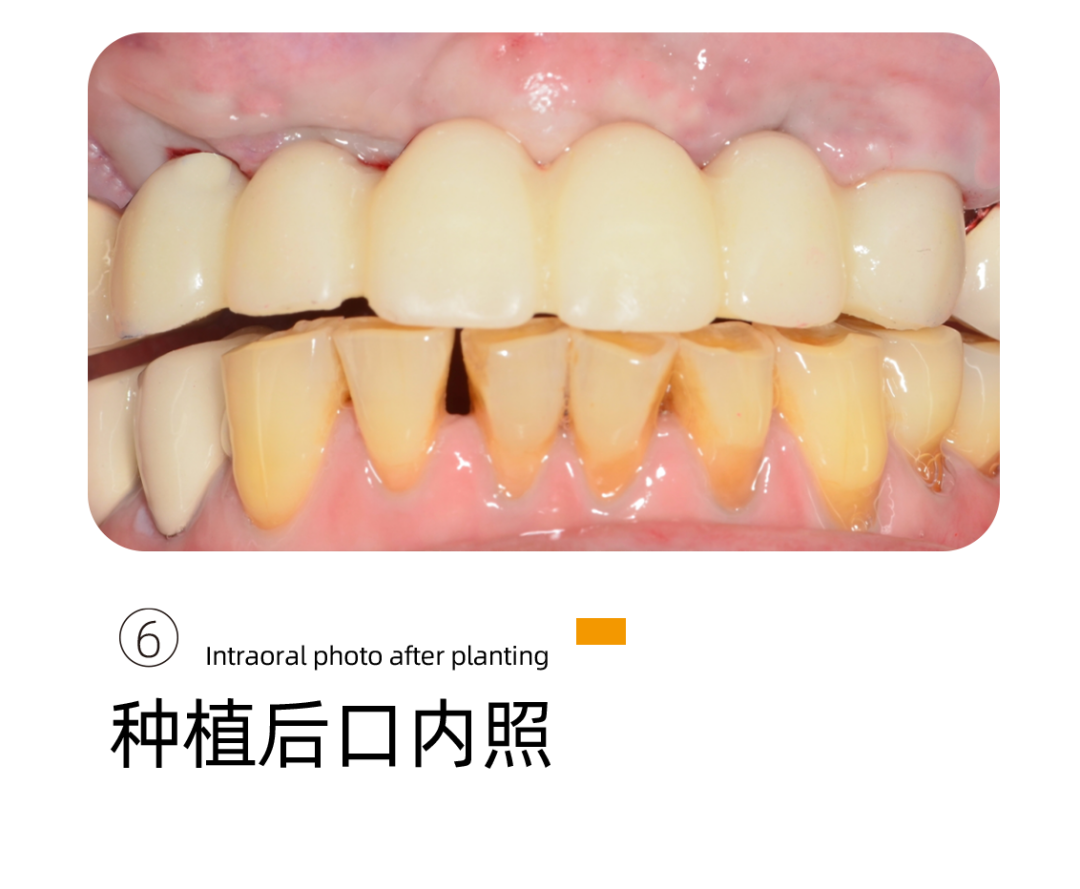

下牙种植完成后,阿姨的感受很好,基本没有疼痛感只有稍微的不适应,重新找回的牙齿让阿姨多了很多生活的幸福。

当天,阿姨就带上了牙 ,恢复了咀嚼的功能。

细致又专业,在手术的过程中注重交流,注重细节,”手很轻“。种植当天就可以吃东西,找回了久违的幸福。